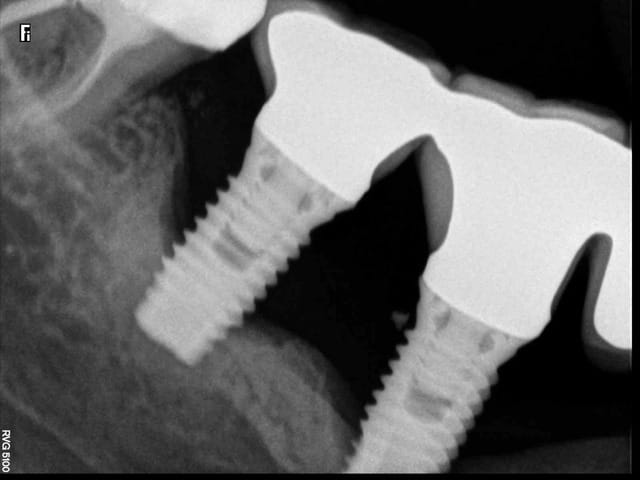

Là je doit déposer celui ci sur 47 (je l ai posé en 2006) et suite à une péri implantite je préfère l enlever.

à mon humble avis, après séparation des couronnes, les quelques spires restantes semblent être dans un os D4 voir même fibrose au pourtour, devrais pas résister beaucoup

flic flac, il ne suffit pas de dire à mon humble avis ( ne le prends pas mal c'est pas mon intention) car deux ou trois spires peuvent avoir une résistance incroyable. Il y a un mois j'ai dû déposer un WP posé par un confrère il a 4 ans avec 3 spires qui restaient intégrées, le tourne à gauche s'est cassé, le davier restait inefficace, et j'ai dû carotter autour pour le déposer car comme toi, en voyant la radio, je pensais que c'était facile.

Le cas que tu présente, les spires sont dans de l'os D1

(corticale) tandis que l'autre cas l'os est vraiment de faible densité.